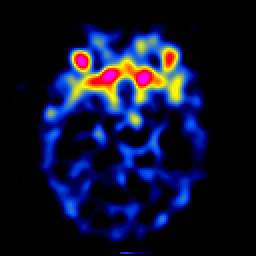

SPECT TL Study #4 -- Slice #20